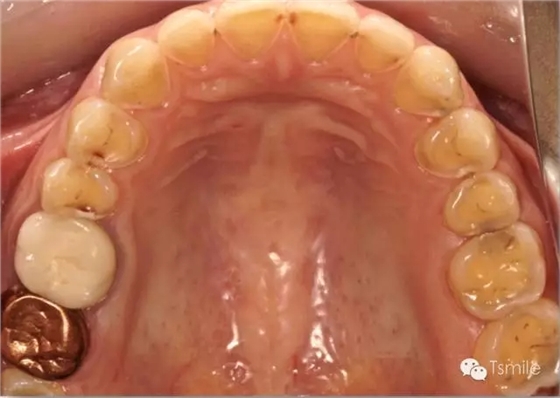

① 神經(jīng)性貪食癥(bulimia)

神經(jīng)性貪食癥是患者由于心理性原因在飲食后自我催吐,混有胃液的嘔吐物進(jìn)入口腔內(nèi),接觸牙齒表面,對(duì)牙齒硬組織造成嚴(yán)重酸蝕脫礦。由于患者在嘔吐時(shí)的特定體位,神經(jīng)性貪食癥導(dǎo)致的牙列重度磨耗主要發(fā)生于上前牙的舌側(cè)、或者累積上頜前磨牙的舌面。

圖4: 神經(jīng)性貪食癥導(dǎo)致的上頜前牙舌側(cè)重度磨耗